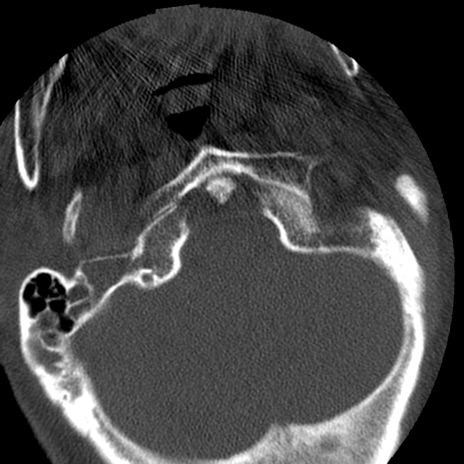

症例50 頚椎CT(横断像)

【症例】60歳代女性

【主訴】後頭部〜右後頸部にかけての痛み

【現病歴】本日飲食店でコーヒーを飲んでいたところ、突然後頭部〜右後頸部にかけて痛みが出現し、右上肢の感覚障害を伴ったため救急要請。

【身体所見】脳神経学的に明らかな異常所見を認めず。右上肢に軽度の感覚障害あり。

異常所見と診断は?

頚椎CT